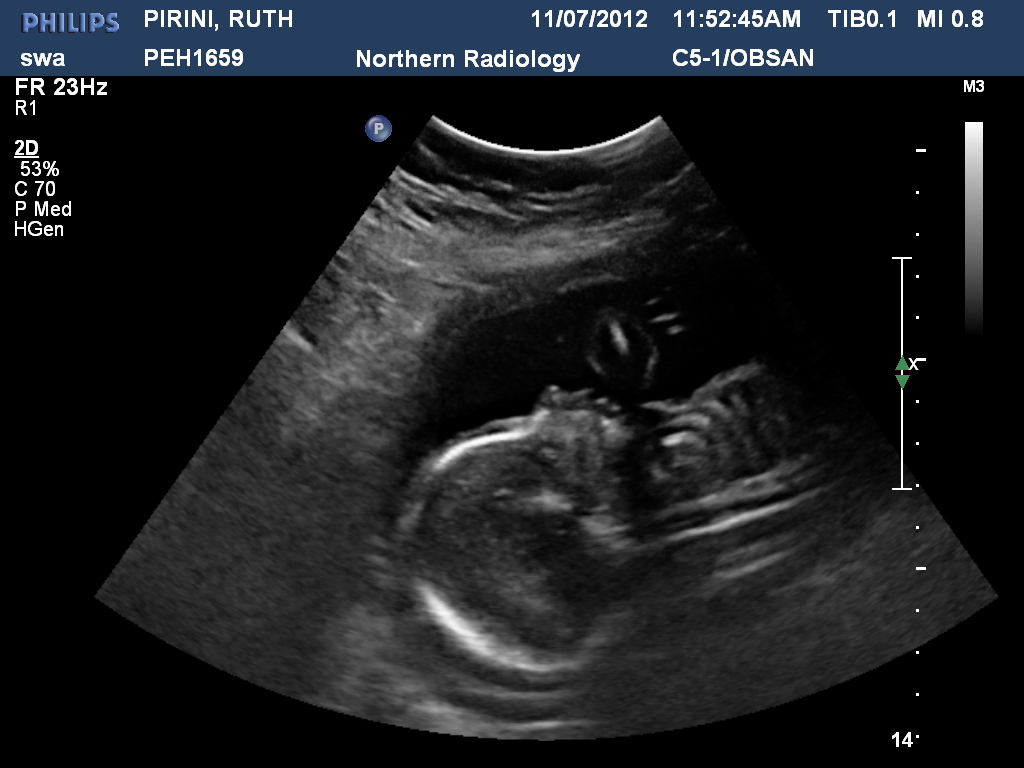

In the holidays we went for our 20 week scan. We were hoping for some 3D images and a video but were disappointed & also not that impressed with the staff at the Radiology centre. O well, we still got to see our little one & were again blown away by the amazing ness of the technology to see & even more than that the little creation that God has allowed to grow within me.

We found out we were having a little girl, which came as a bit of a surprise! They measured everything and pointed out the different parts -- I think for me the feet were the cutest, measuring just 3cm & so perfectly formed. But it was also interesting to see the blood pumping through the 4 heart chambers and all the other parts. The head measured quite small for her age, but we were assured that it was probably just because of the position she was in.

Here are a few photos -- see if you can figure out what is what!!